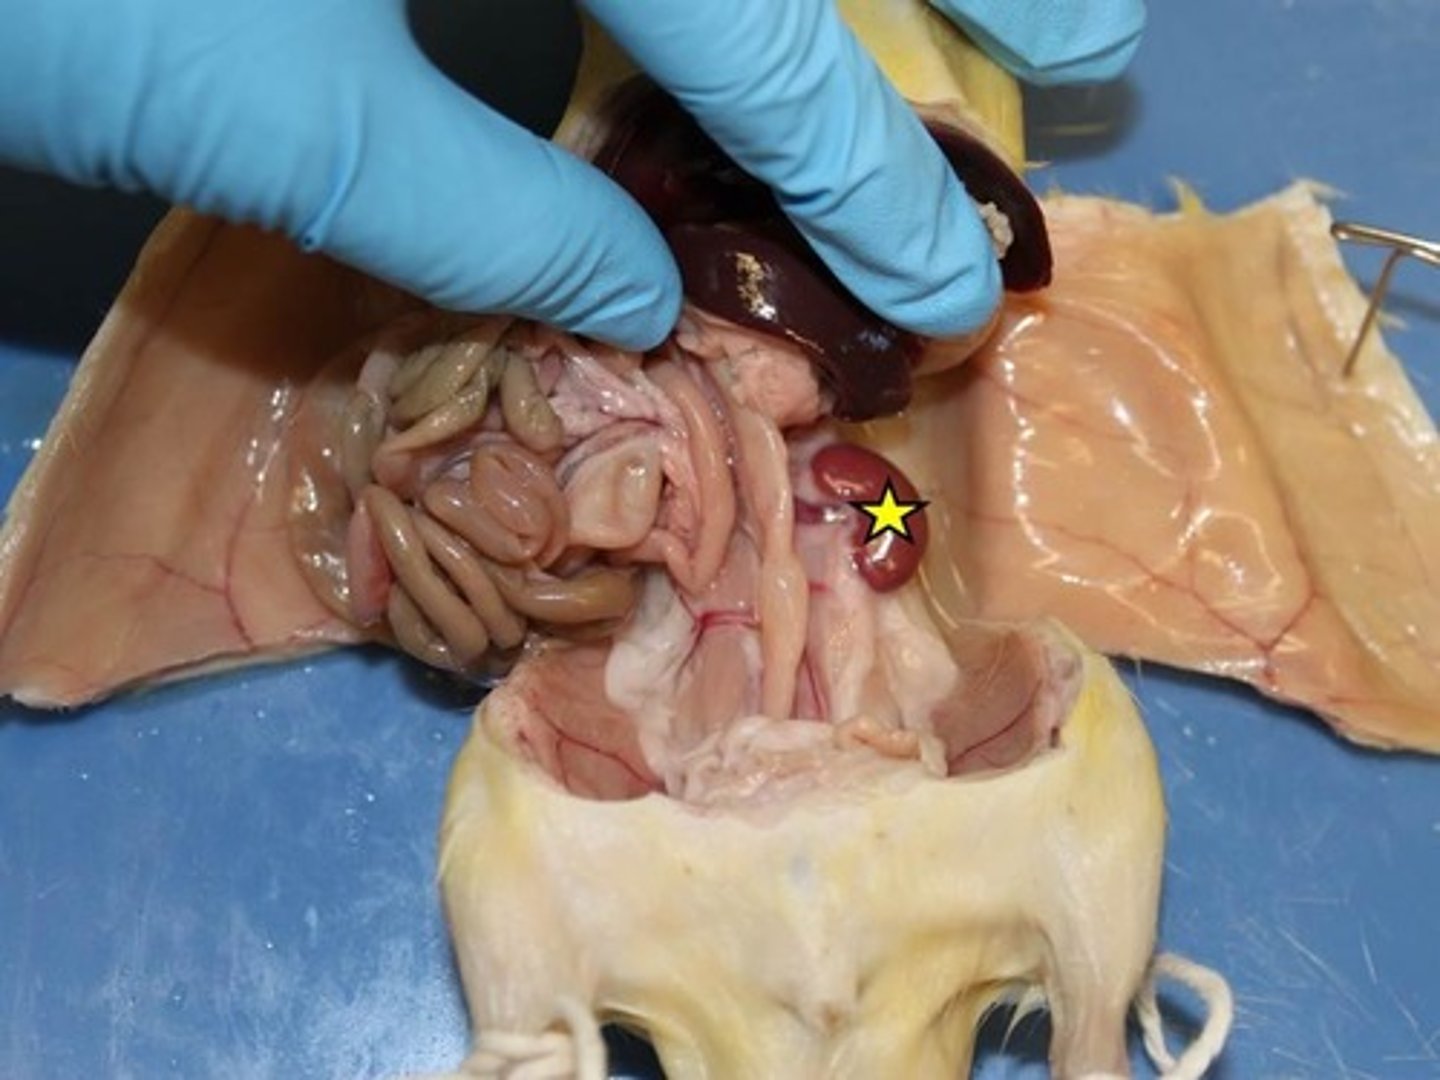

kidney

spleen